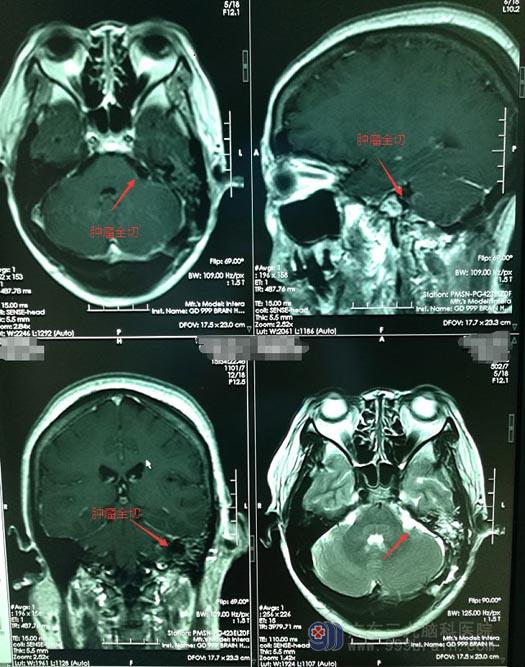

向患者和家属详细交代病情后,在全麻下为郑阿姨行“左侧桥小脑角脑膜瘤切除术”,术中见肿瘤位于左侧桥小脑角,在三叉神经及面听神经之间,基底位于岩骨部,周围血管包绕,血管丰富,质稍韧,界限清,直径约1.5cm,将肿瘤全切,过程顺利,周围血管及颅神经保护完好,术中出血约200ml。

▲手术后

术后,郑阿姨恢复良好,肢体活动有力,无头痛头晕、肢体麻木、语言障碍等不适症状。